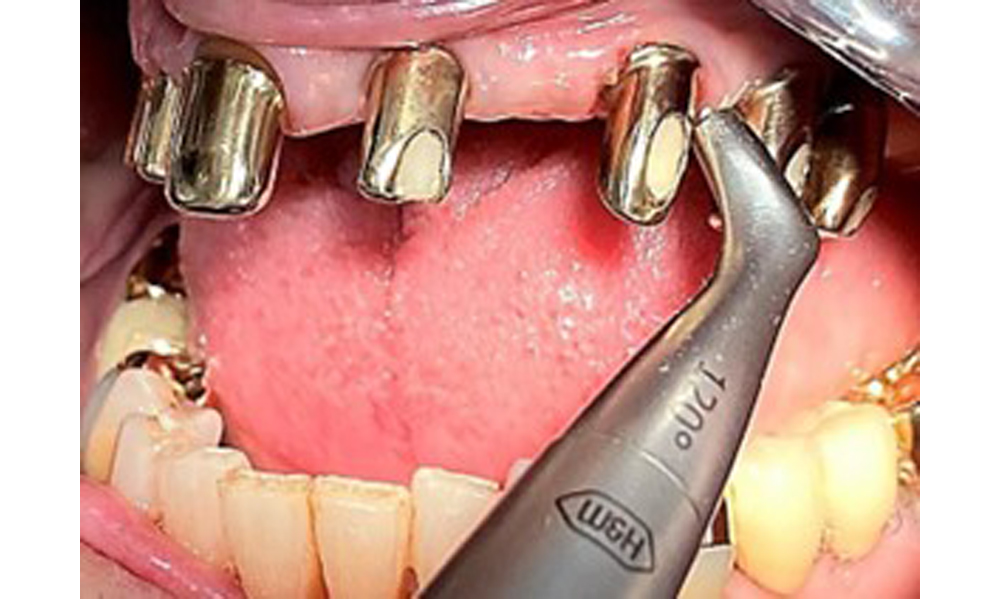

The patient was fitted with a combined removable maxillary telescopic prosthesis more than 25 years ago (Fig. 1, Fig. 2, Fig. 3) and is very happy with her dentures. The patient has an adequate fixed denture for the mandible (Fig. 4).

Frontal view with the maxillary denture in situ.

Fig. 1: Frontal view with the maxillary denture in situ.

The dental findings are as follows: Combined removable implant and tooth-supported telescopic prostheses on implants 15, 13, 21, 23, 24, 25 and tooth 11 (Fig. 1, Fig. 2, Fig. 3). The patient was fitted with a fixed mandibular denture. Adequate bridges were present over 37 to 34 and 45 to 47 (Fig. 4), the crown margins were intact and there were no active caries. A composite filling with a marginal gap was present on tooth 43. There was mandibular gingival recession, exposing 1 to 3 mm of root surface. This also applies to 11.